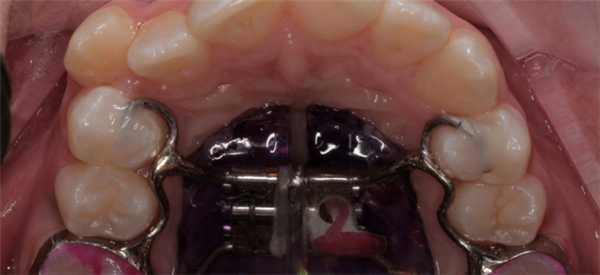

Конструкция аппарата Дерихсвайлера

- Основа - пластина изготовлена из металла или пластмассы. Если остановиться на выборе материала, то металл - это достаточно жёсткий материал, поэтому может вызвать определённый дискомфорт. Однако применение металлических конструкций значительно сокращает сроки лечения. Если говорить о пластмассовых аппаратах - удобны при использовании, но неспособны обеспечить должное давление, благодаря чему сроки исправления дефектов увеличиваются в разы. Также существуют комбинированные варианты.

- В середине основы расположен металлический винт, аппарат дерихсвайлера подкручивать придётся самостоятельно, чтоб увеличить площадь пластины (принцип работы системы рассмотрим ниже).

- По краям основа имеет кольца-крючки (своеобразные дуги фиксаторы), изготовленные из металла в 1-1,2 мм. Эти фиксаторы крепятся к молярам или премолярам. В зависимости от вида патологии могут крепиться и на клыки.

- Как дополнительные элементы конструкция может иметь разнообразные пружинки и винты. Их задача поспособствовать удалению или предотвращению образования щелей между зубами. Иногда в процессе расширения нёба, такой эффект возникает благодаря смещению зубных единиц.

Аппарат Дерихсвайлера изготовляется индивидуально, с учётом размеров ротовой полости и существующих проблем у пациента.

Аппарат устанавливается так, чтоб его основа была по центру нёба. Фиксация основы производится благодаря кольцам, которые надеваются на опорные зубы. Установленный аппарат создаёт определённое давление на челюстные дуги, постепенно расширяя верхнюю челюсть в поперечном направлении и тем самым делая её шире. Увеличивается нагрузка давления при помощи металлического винта, который находится в основе системы. Пациенту составляется график, когда именно и насколько нужно сделать обороты винта.

Аппарат Дерихсвайлера изготовление и установка

- Перед изготовлением и установкой препарата, врачу потребуется немного раздвинуть опорные зубы. Для этого между зубными единицами устанавливаются специальные сепарационные кольца - колечки из резины. Эта процедура займёт 5-10 мин. Зубы начнут смещаться, а пациент первое время будет ощущаться ноющую боль. На время ношения колечек нельзя употреблять вяжущую пищу и жвачки. Если резинка вывалится, её можно установить самостоятельно. Для этого можно воспользоваться обычными нитками. Аккуратно устанавливая резинку растягивая её края.

- На втором этапе врач вынимает резиновые кольца, и создают слепок для будущей конструкции. После этого кольца размещают по своим местам. Период, когда изготавливается система, можно посвятить основательной чистке зубов. Образовавшиеся промежутки как раз помогут добраться до труднодоступных мест.

- После изготовления конструкции происходит её примерка. Если всё подошло идеально, аппарат устанавливается и фиксируется. Первое подкручивания винта производит сам врач, подбирая оптимальную силу воздействия конструкции на челюсть. Затем процедуру подкручивания будет проводить сам пациент. Для этого врач создаёт определённый график, которого нужно обязательно придерживаться. Для каждого пациента он свой. Если говорить о средних показателях, вначале процедура повторяется 1 раз на 3 дня, в последующем ежедневно.